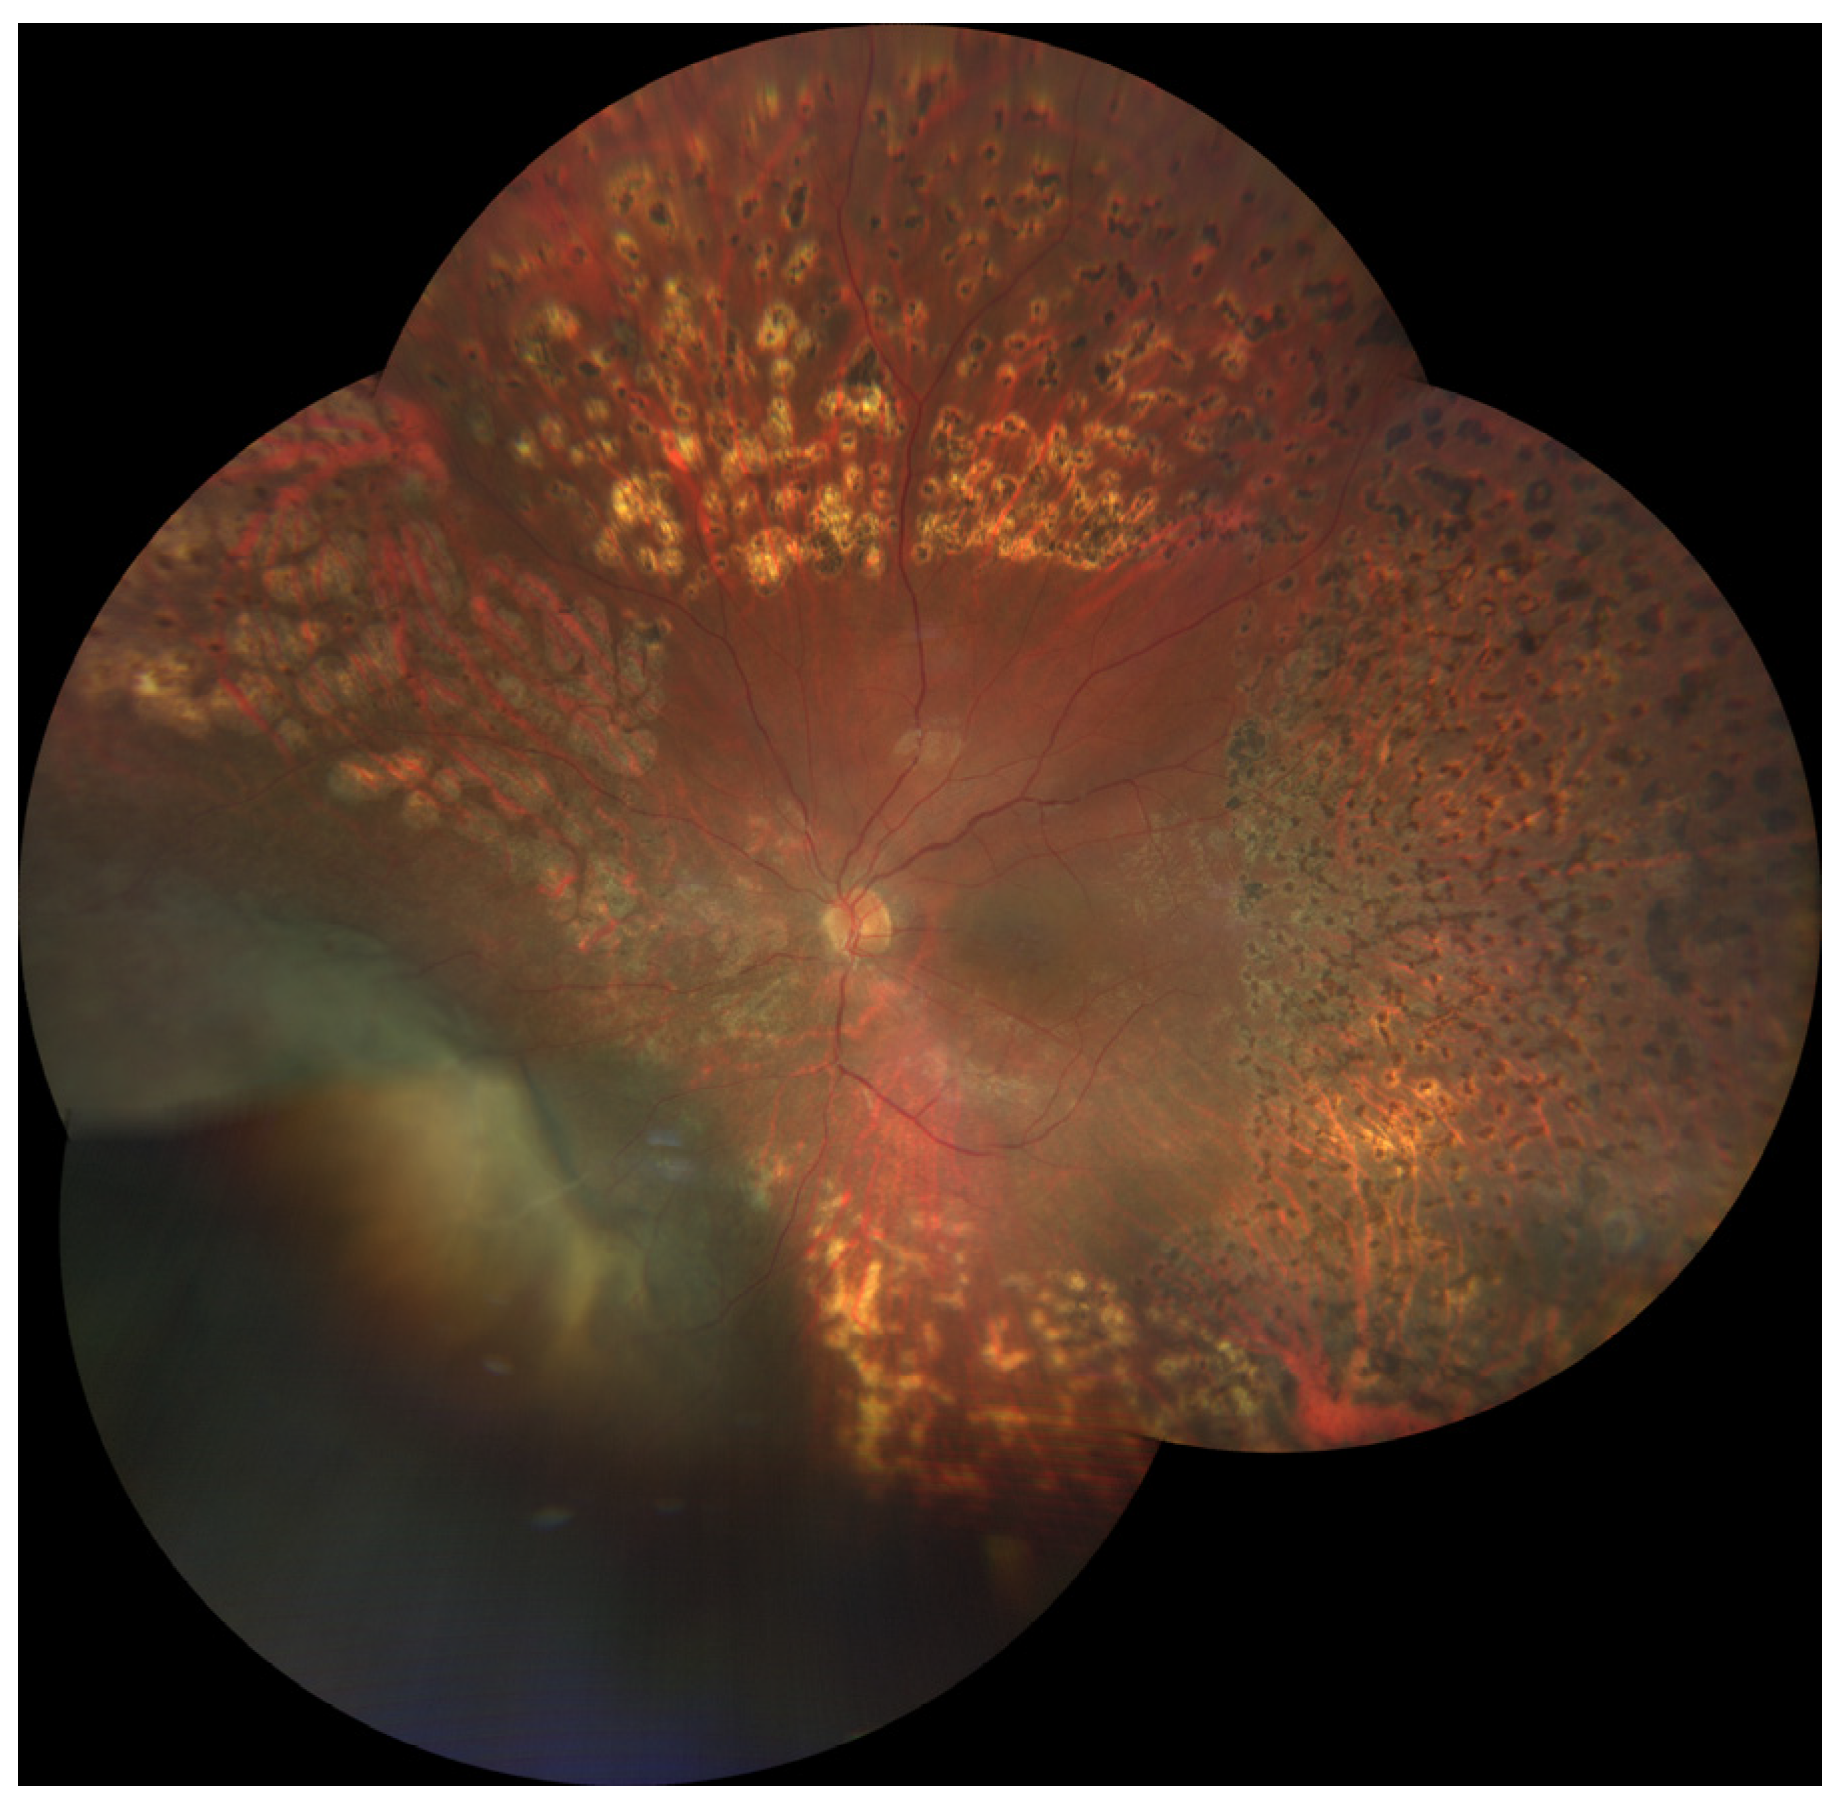

3.1. Radiation (Chorio)Retinopathy

3.2. Radiation Maculopathy